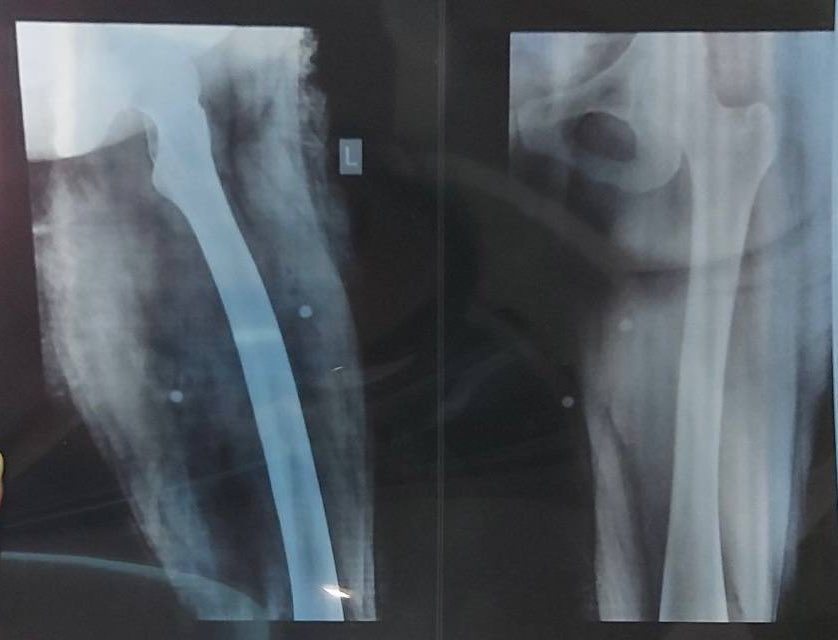

بچهها یکی مشاورهی پزشکی فوری میخواد که بدونه باید جراحی کنه یا نه:

ساچمه خورده توی زانو و کشالهی رونش. دو تا دکتر گفتن که اونی که تو زانو هست رو میشه دراورد، ولی اون بالاییها دراوردنش خطرناکه چون نزدیک عصب هست و ممکنه عصب رو از کار بندازه.

راه رفتنش بهتر شده ولی هر حرکت کششیای خیلی درد داره و حموم که میره بعدش دور زخمها خیلی کبود میشه.

بهم دیرکت بدین اگه دکترین و میتونین راهنمایی کنین لطفا.